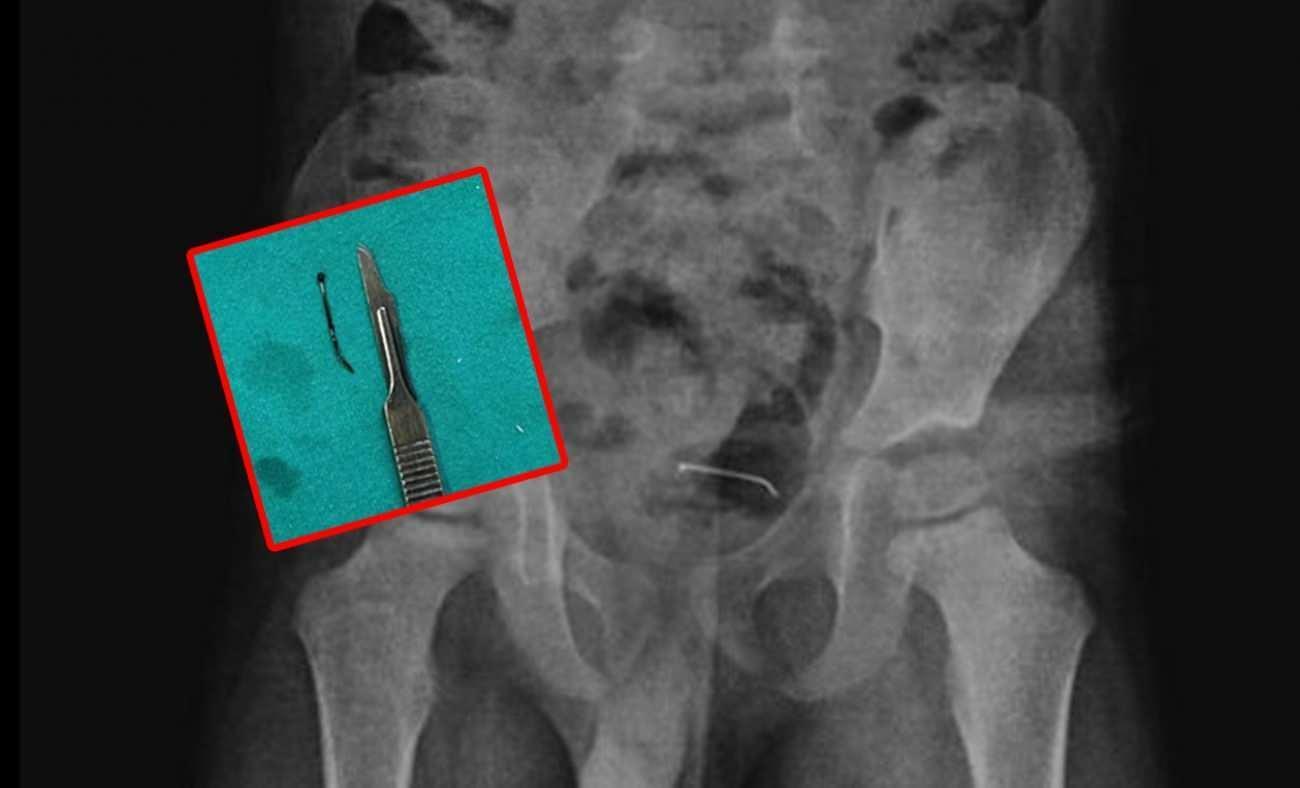

5 yaşındaki çocuğa yapılan tetkikler sonucunda, şiddetli karın ağrısına neden olan durumun mesane duvarına yapışan yabancı unsur olduğu tespit edildi. Küçük çocuğun yuttuğu 3 santimetre uzunluğundaki toplu iğne başarılı bir operasyonla alındı.

Kamçı, yabancı cismin bedenden olağan yollarla atılamadığını belirterek, “Bunun üzerine ameliyat kararı aldık. Ameliyatta cismin mesane duvarına yapıştığını gördük. Cerrahi operasyonla 3 santimetre civarındaki toplu iğneyi çıkardık. Hastayı birkaç gün takipte tuttuk. Genel sıhhat durumu âlâ olan hastamızı taburcu ettik.” ifadelerini kullandı.